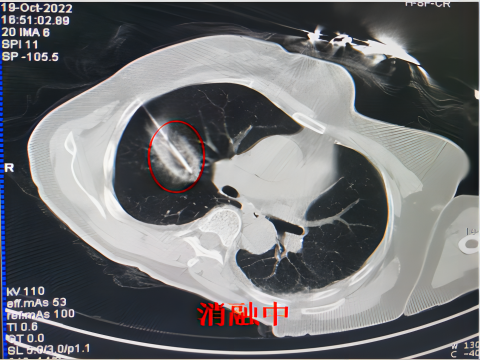

肿瘤在进行冷冻消融后,冷冻区域的“病灶”可能会显示扩大,这是正常的病理变化,只要术后按期随访观察,一般情况下,半年至一年内会吸收完全。